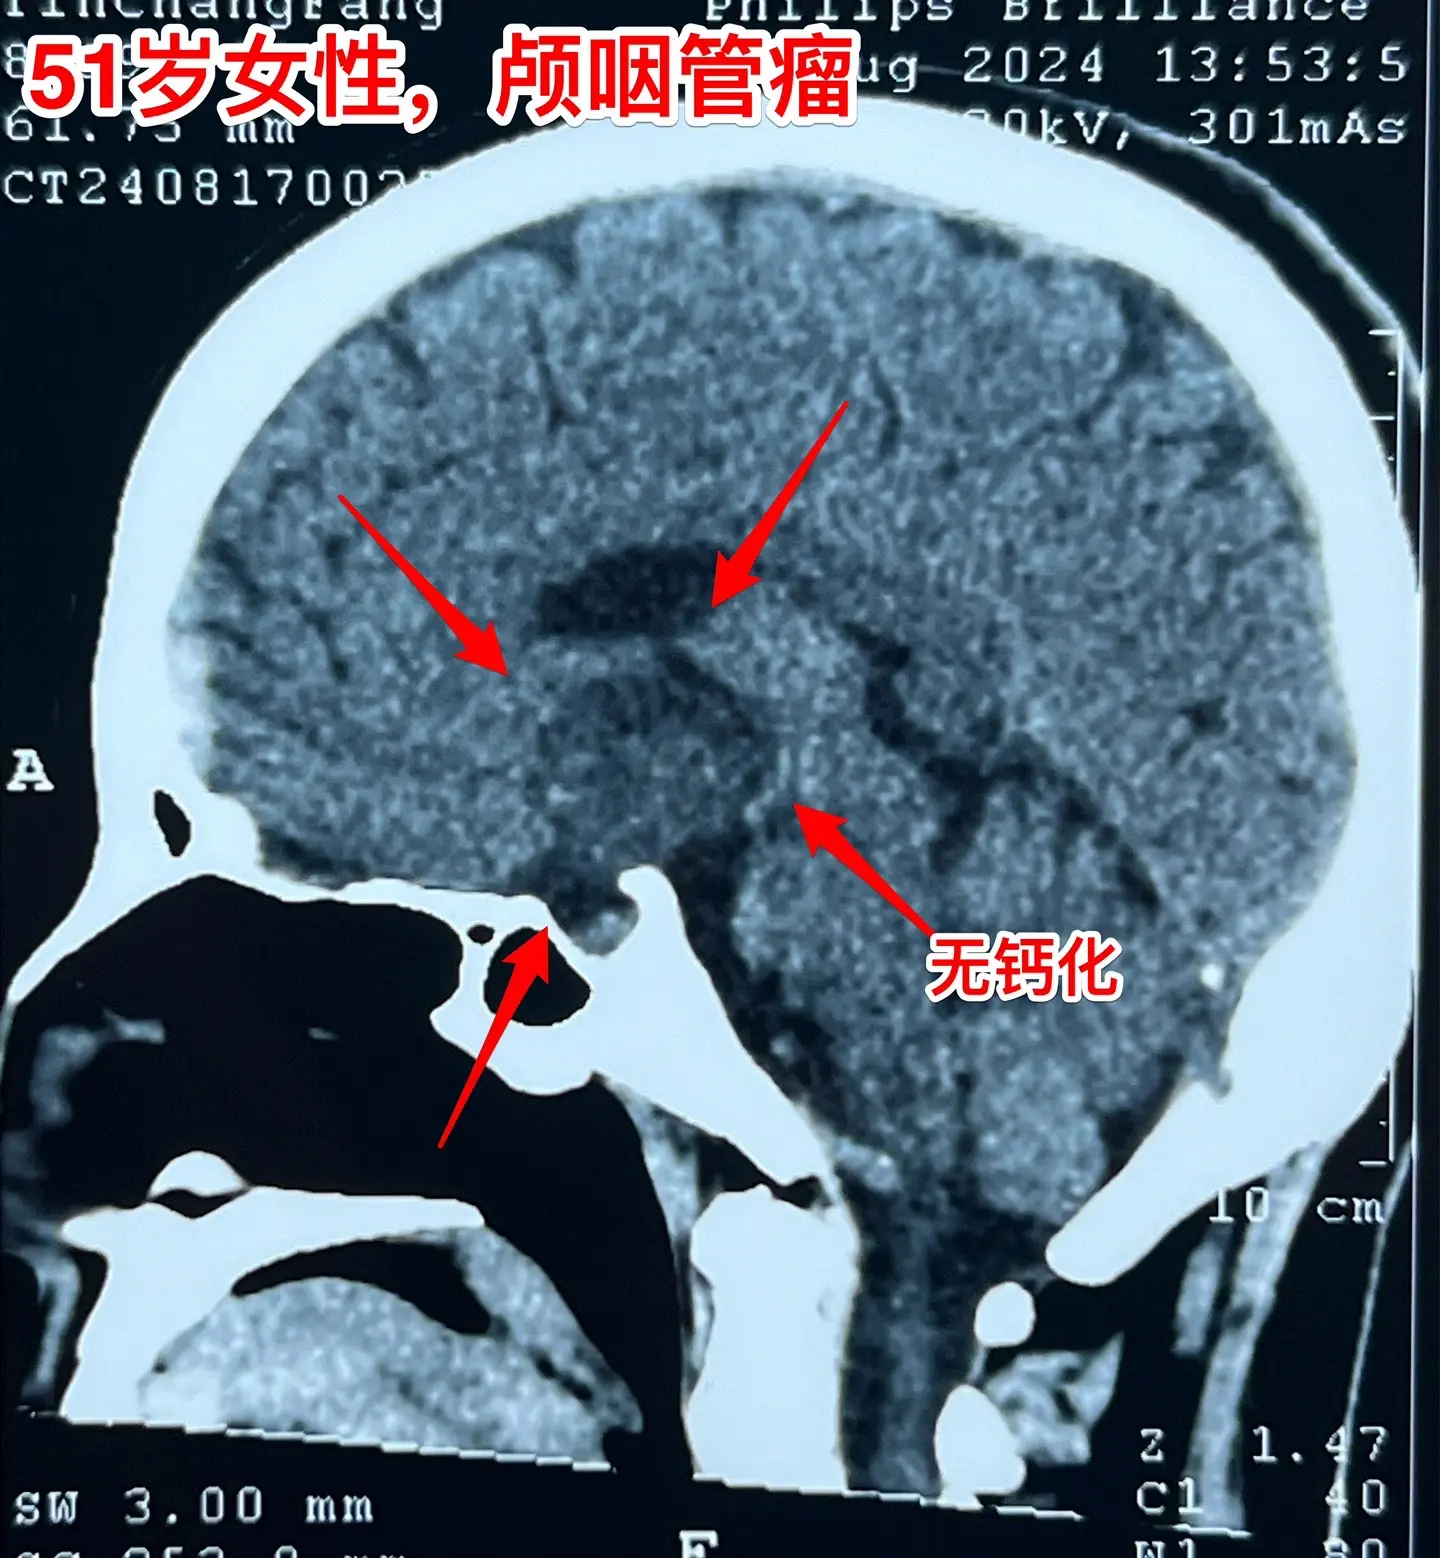

视频中展示出来的是第一个和第三个病人的影像学资料。

第一个病人女性,51岁,山东人。患者的弟弟就是神经外科医生。病人因为视力下降、困倦、无精打采到医院检查发现颅咽管瘤,是乳头型颅咽管瘤。患者家人一致要求作开颅手术切除颅咽管瘤。今天的手术很顺利,颅咽管瘤得到完全切除,晚上病人作完了CT就从ICU转到普通病房了。